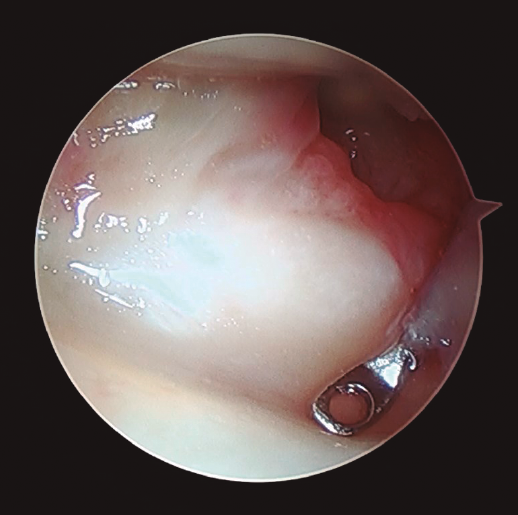

Para clasificar las alteraciones de las partes blandas se recurrió a la clasificación de Palmer(24) y Atzei(25) en el caso de afectación del CFCT (Tablas 1 y 2) y a la clasificación de Geissler/Lindau(3,7,9) para las lesiones de los ligamentos intrínsecos de la muñeca (Tabla 3). En el caso de detectar lesiones asociadas en las partes blandas articulares, se procedió a evaluar la necesidad de realizar un tratamiento simultáneo de las mismas. Las lesiones observadas fueron subsidiarias de tratamiento quirúrgico asociado cuando se encontraron los siguientes hallazgos artroscópicos:

Figura 4. Desde el portal de visión radiocarpiano 3-4 se explora con el instrumental en el portal 6R el complejo del fibrocartílago triangular, observando pérdida de tensión del mismo.

- La pérdida de tensión del CFCT (signo del “trampolín”) con posibilidad de introducir el instrumental artroscópico por debajo del mismo (prueba del “gancho”)(26,27)(Figura 4). De acuerdo con la clasificación de Palmer(24), estas lesiones se trataron de la siguiente manera: tanto las lesiones de tipo IA como ID se trataron mediante un desbridamiento simple con sinoviotomo de 2,5 mm(26,27,28). En el caso de las lesiones de tipo IB y siempre que se observó una prueba del “gancho” positiva, se realizó una reinserción mediante sutura a cápsula articular o un reanclaje a fóvea, según correspondiese en cada caso(26,27,28).